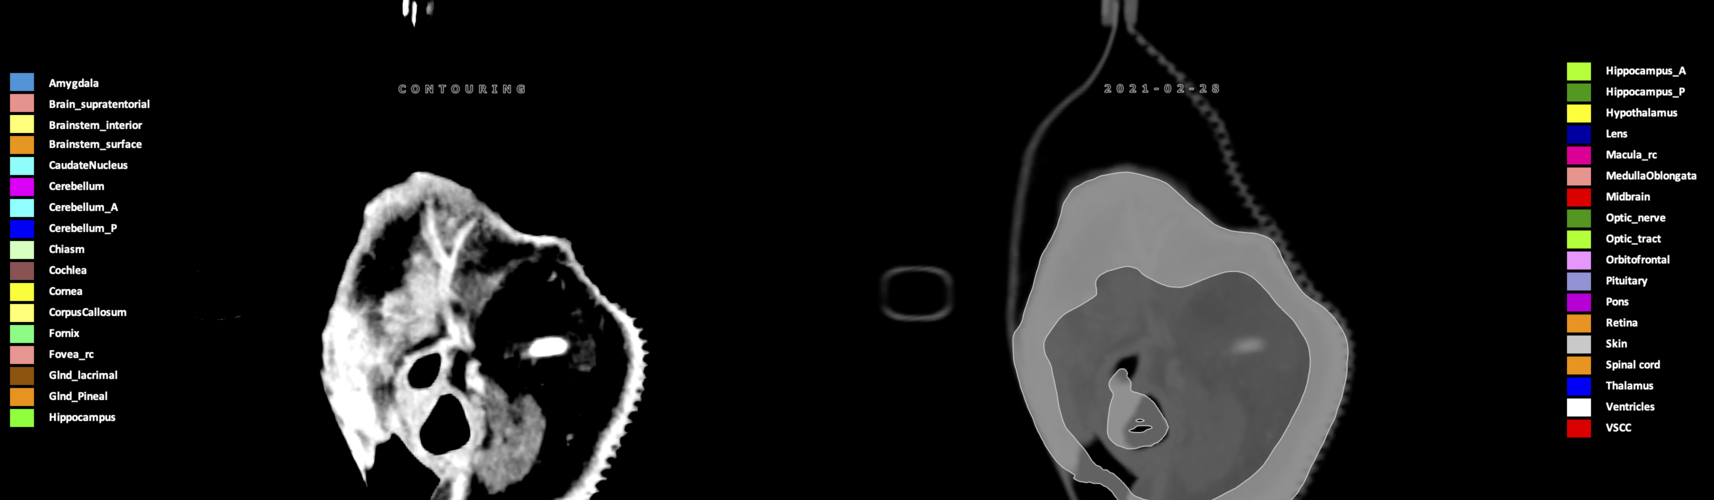

Eekers et al. have published an international neurological atlas for contouring of organs at risk in consensus with the European Particle Therapy Network (EPTN) in 2018 and an update in 2021. The purpose of this consensus atlas is to decrease inter- and intra-observer variability in delineating OARs relevant for neuro-oncology.

Included are all OARs known to be relevant for radiation-induced toxicity in neuro-oncology: brain, brainstem (midbrain, pons, medulla oblongata), chiasm, cerebellum (anterior & posterior), cochlea, cornea, hippocampus (anterior & posterior), hypothalamus, lens, lacrimal gland, optic nerve, pituitary, skin, and vestibular & semicircular canals. To further facilitate research on cognition, vision and radiological changes after irradiation of the brain, potential clinically-relevant OARs are included: amygdala, caudate nucleus, cerebellum (anterior & posterior), corpus callosum, fornix, macula, optic tract, orbitofrontal cortex, periventricular space (PVS), pineal gland, and thalamus.

Three-dimensional delineation of the 25 consensus OARs for neuro-oncology are shown on CT (WW/WL 120/40, 3000/600), 3T MR images, (T1Gd, T2FLAIR 1mm) and 7T MR (MP2RAGE 0.7 mm). All are presented in transversal, sagittal and coronal view.